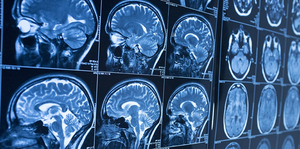

- Differentiate between different radiological modalities.

- Know the common terminology used in describing in different radiological modalities.